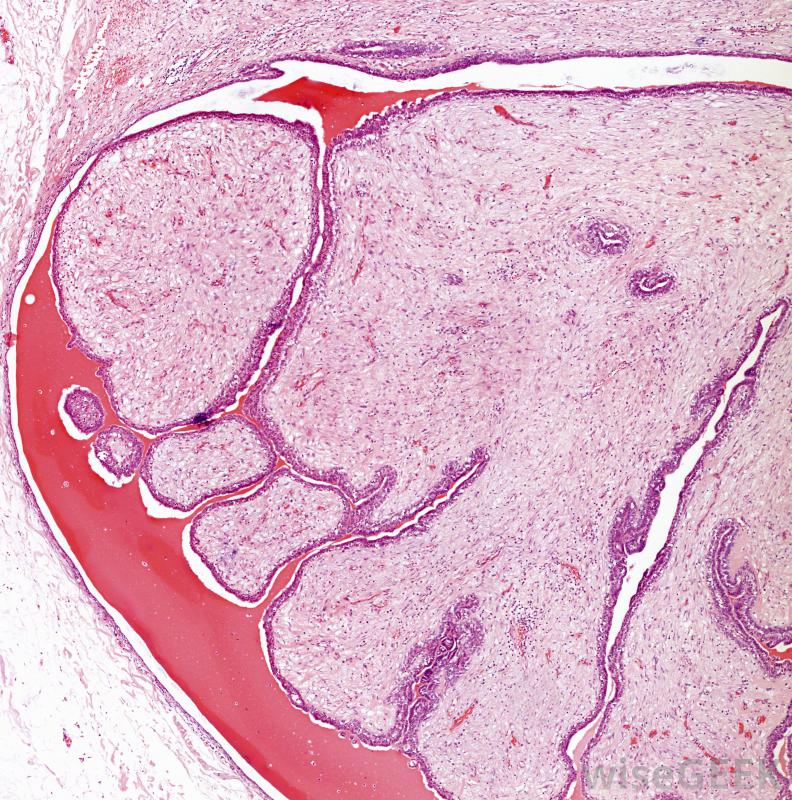

常見的低回聲病變可能包括纖維腺瘤或乳腺囊腫。

腎臟低回聲病變可能是常見的,良性腫瘤稱為纖維腺瘤或乳腺囊腫。如果病變不正常或不符合某些標準,例如一端有深色陰影,含有鈣化點,或顯示其他一些不尋常的、明確的特征,衛生保健人員可能會懷疑是癌癥。隨后的檢查可能包括針活檢包括用針頭和注射器提取細胞。肝臟病變:肝細胞腺瘤,也稱為肝細胞腺瘤,和肝血管瘤都是良性腫瘤,在超聲上可產生低回聲病變。這些腫瘤通常被切除,尤其是在引起不適的情況下,為了避免它們變成癌細胞的風險。飲酒、肥胖和糖尿病是脂肪沉積的一些常見原因,這些脂肪沉積在肝臟上表現為病變;根據病因的不同,有可能逆轉這些沉積。肝癌也可能表現為低回聲;通常,計算機斷層掃描(CT)是用來正確診斷肝癌的。前列腺病變:前列腺癌在超聲上幾乎總是表現為低回聲病變。醫療人員可以通過血液測試、針活檢或進一步的成像研究來診斷惡性低回聲病變。細菌、真菌,或者病毒感染可以導致前列腺炎,也可以表現為低回聲病變。甲狀腺病變:大多數甲狀腺病變是良性的,非常常見。患有甲狀腺過度活躍或活動不足的人會出現甲狀腺腫大,通常稱為甲狀腺腫該區域的低回聲病變可能只表明甲狀腺腫大或感染。自身免疫性疾病也會影響甲狀腺,導致橋本氏病。甲狀腺癌可以是低回聲的,通常很容易治療。腎臟病變:低回聲病變也可以出現在腎臟上,可能表明腎結石或腎囊腫一樣常見的東西。都會引起腹痛,通常需要治療。腎細胞癌或腎癌,也可能表現為低回聲病變,需要額外的放射學檢查才能正確診斷。